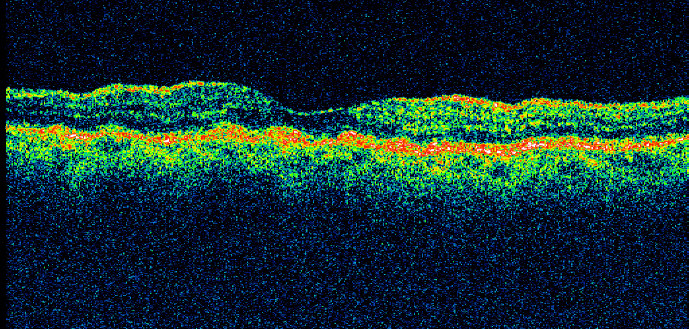

Trockene AMD (~90%)

Sie beginnt mit Problemen bei der Entsorgung von Ablagerungen der Stoffwechselprodukte (Drusen = Schlacke). Im weiteren Verlauf kann es zu einem Absterben der Sehzellen durch Hypoxie und damit zum Sehverlust im Netzhautzentrum kommen.

Feuchte AMD (10- 15%)

Die trockene Form der AMD kann in eine feuchte Form übergehen, d.h. es entstehen unter der Netzhaut neue Gefäße (CNV), die bluten können, daher die Bezeichnung "feuchte AMD". Es kommt zu einer plötzlich auftretenden Sehverschlechterung.

Pathogenese

Oxidationsprozesse: Die hohe Sauerstoffrate und intensive Phototransduktion im Makulabereich führt zur Anreicherung toxisch freier Radikale.

Der Metabolismus des retinalen Pigmentepithels (RPE) wird zunehmend unvollständiger, Lipidresiduen akkumulieren in den RPE-Zellen. Diese führen zu einer enzymatischen Autolyse und zum Zelluntergang. Dadurch treten Veränderung der Bruch-Membran ein. Dieser Defekt führt zu Permeabilitätsstörung und zur Hypoxie mit Aktivierung der inflammatorischen Stimuli.